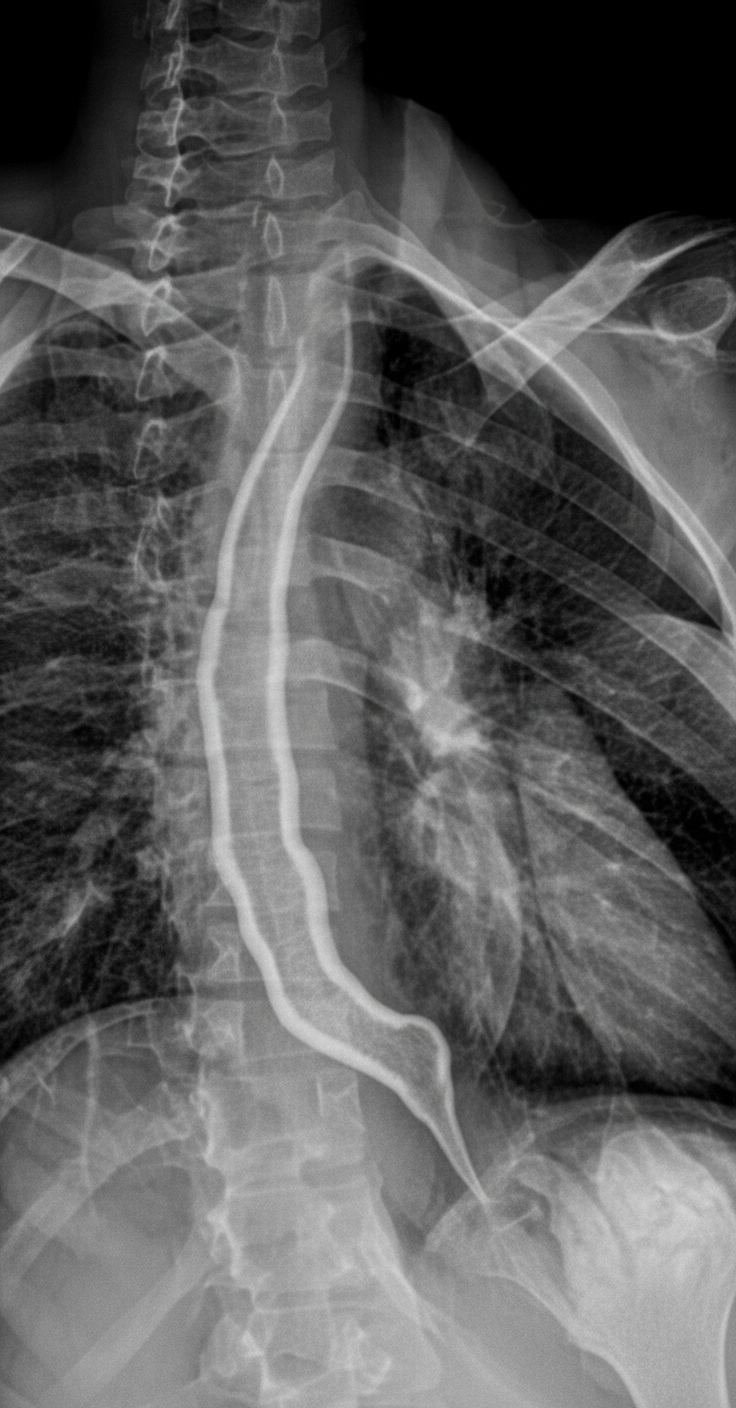

What is the diagnosis demonstrated in the barium esophagogram?

Explanation: ***Carcinoma esophagus*** - Shows classic **rat-tail** or **apple-core appearance** with irregular stricture and **shouldering** on barium esophagogram. - Demonstrates **abrupt cutoff** with mucosal irregularity and asymmetric narrowing characteristic of malignant lesions. *Achalasia* - Presents with **bird-beak appearance** showing smooth, symmetric tapering at the gastroesophageal junction. - Associated with **esophageal dilatation** proximally and absence of the irregular stricture seen in malignancy. *Schatzki's ring* - Appears as a **smooth, thin ring** at the gastroesophageal junction without irregular margins. - Represents a **benign web** that causes intermittent dysphagia, lacking the shouldering of carcinoma. *Nutcracker esophagus* - This is a **functional disorder** with no characteristic findings on barium esophagogram at rest. - Diagnosis requires **manometry** showing high-amplitude peristaltic contractions, not radiographic abnormalities.